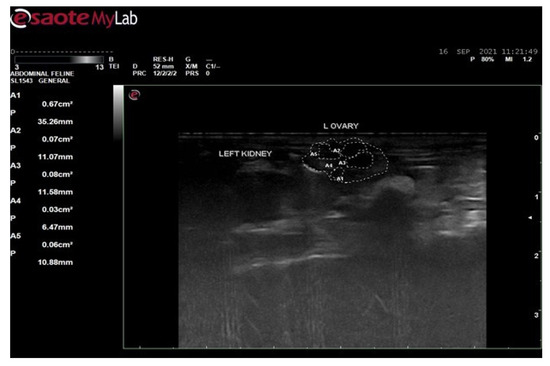

3.6. Ultrasound Examination for Diagnosis of PCOS

3.6.2. Ultrasound Examination of Female Rats of Disease Group